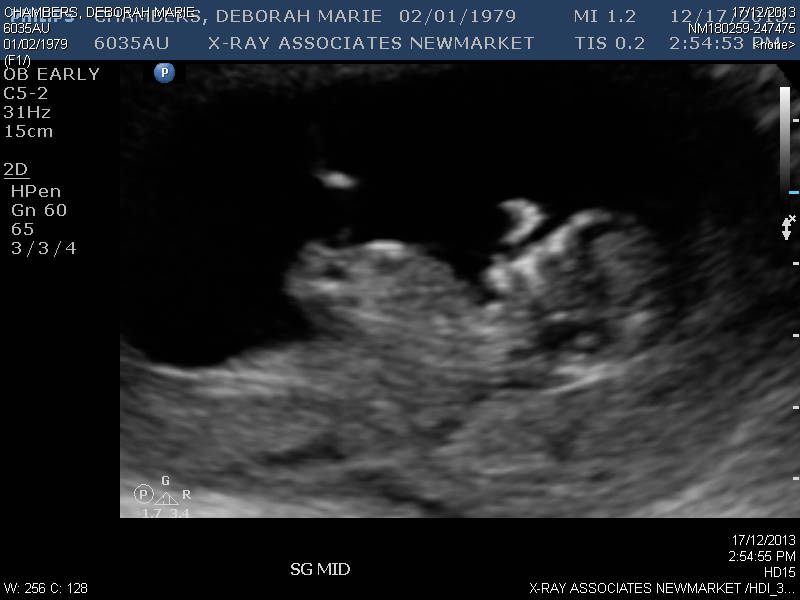

I have tired and tired and looked at so many sites tonight and my eyes hurt! I would love some guesses as to if this is a girl or a boy nub :)Attachment 15758Attachment 15760